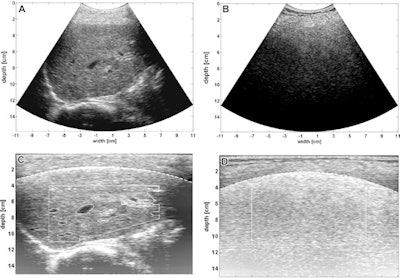

(Left) Calibrated ultrasound software shows a normal liver. (Right) Images show nonalcoholic fatty liver disease on an activity score grade-3 liver. Images A and B show original B-mode images with applied lookup table correction. Images C and D are back-scanned images with applied post-processing steps. These steps included automatic gain correction, superficial tissue layer correction, automatic segmentation, and residual attenuation correction. Images courtesy of the RSNA.The team found that the average calibrated ultrasound interobserver correlation coefficient was 0.95, and that the best correlation with steatosis was found for the RAC parameter (r = 0.78, p < 0.01). However, no correlation was found for fibrosis (r = 0.14, p = 0.054).